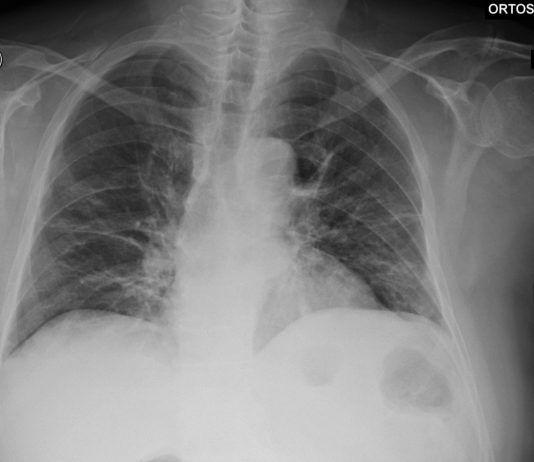

55-year-old male

patient with onset of cough and fever on February 24, in quarantine due to a

known contact with a Covid-19 patient. No previous medical...